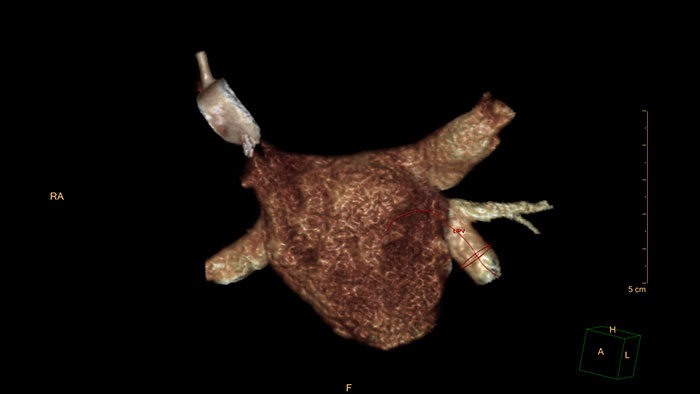

Detailed 3D visualization of the segmented heart

MR Cardiac Whole Heart performs automatic segmentation of the heart into individual segments (e.g. LV, RV, atria, and coronaries).

Benefits